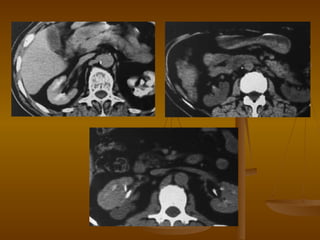

КТ почек Нативное исследование Паренхиматозная фаза  контрастирования Лоханка Ветви почечной артерии MeduMed.Org -  Медицина - Наше Призвание

Реконструкции почек Кортикальная фаза контрастирования Корковое вещество Мозговое вещество MeduMed.Org -  Медицина - Наше Призвание

3 D  ангиография почек Общая подвздошная артерия Брюшная аорта Почечная артерия Чревный ствол MeduMed.Org -  Медицина - Наше Призвание

Почечные артерии (норма) 3Д (затененный объем) MIP (проекция макс. интенсивности) МПР (мультипланарная реконструкция) MeduMed.Org -  Медицина - Наше Призвание